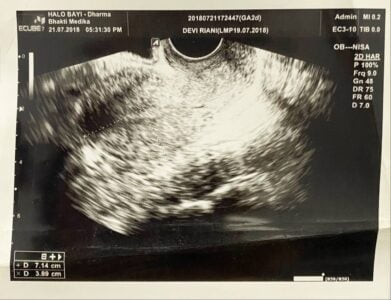

Inilah hasil usgnya, Pada saat itu, biaya untuk menjalani pemeriksaan USG transvaginal cukup terjangkau, hanya 200 ribu rupiah.

Tapi tiba-tiba, saya cek hasil pemeriksaan yang menyebutkan dugaan PCOS dan vaginismus. Bingung, euy…